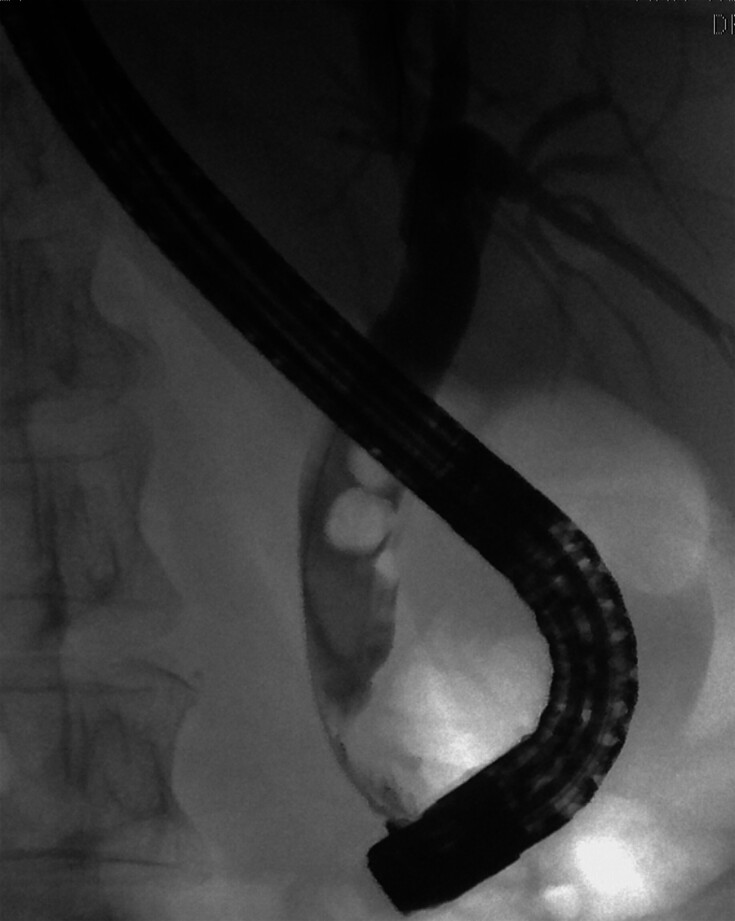

Informed consent was obtained from all patients. All patients received a single dose of prophylactic intravenous antibiotics (third-generation cephalosporin) prior to cholangioscopy. All procedures were performed under moderate sedation with midazolam, propofol, and fentanyl in prone position. If procedure time was expected to be more than 1 hour or at anesthetist discretion, the procedure was performed under general anesthesia with endotracheal intubation. Antibiotic prophylaxis was administered in all patients at the time of the procedure. A therapeutic duodenoscope with a 4.2-mm channel (TJF Q180V, Olympus, Tokyo, Japan) was used for endoscopic retrograde cholangiopancreatography (ERCP). After CBD cannulation, a cholangiogram was obtained and the size of the lower CBD (1 cm proximal to papillary opening) and stone size were measured ( Fig. 1 ). Sphincterotomy size (Ultratome XL, Boston Scientific, Massachusetts, United States) and further balloon dilatation (Hurricane or CRE, Boston Scientific, Massachusetts, United States), was left to endoscopist discretion. If balloon dilatation was performed, balloon size never exceeded the lower extraduodenal CBD diameter, which was measured 1 cm proximal to the papillary orifice. Sphincterotomy was not extended in patients with previous sphincterotomy. Cholangioscopy was performed with the Spyglass DS system (Spyscope DS, digital controller, access and delivery catheter, Boston Scientific, Massachusetts, United States), equipped with an irrigation and aspiration system. The cholangioscope was introduced through the 4.2-mm working channel of the duodenoscope using a free-hand technique ( Fig. 2 ). In case of sharp angulation in the lower bile duct, the cholangioscope was introduced in the CBD over the wire (0.025, Visiglide, Olympus, Tokyo, Japan). We chose 0.025-inch wire because it has similar strength to a 0.035-inch wire and we did not encounter any difficulty with the 0.025-inch wire.